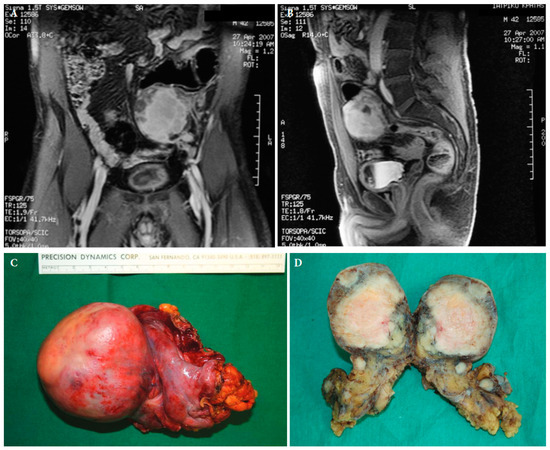

7. Treatment of Local Recurrence

- Gyorki, D.E.; Brennan, M.F. Management of recurrent retroperitoneal sarcoma. J. Surg. Oncol. 2014, 109, 53–59. [Google Scholar] [CrossRef]

- Tseng, W.W.; Swallow, C.J.; Strauss, D.C.; Bonvalot, S.; Rutkowski, P.; Ford, S.J.; Gonzalez, R.J.; Gladdy, R.A.; Gyorki, D.E.; Fairweather, M.; et al. Management of locally recurrent retroperitoneal sarcoma in the adult: An updated consensus approach from the Transatlantic Australasian Retroperitoneal Sarcoma Working Group. Ann. Surg. Oncol. 2022, 29, 7335–7348. [Google Scholar] [CrossRef]